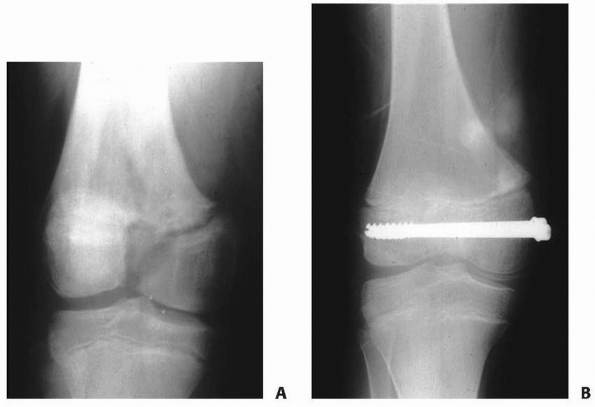

| Figure 5-20 A. Salter-Harris type III fracture of the distal femur. B. Fixation with cannulated screws. |